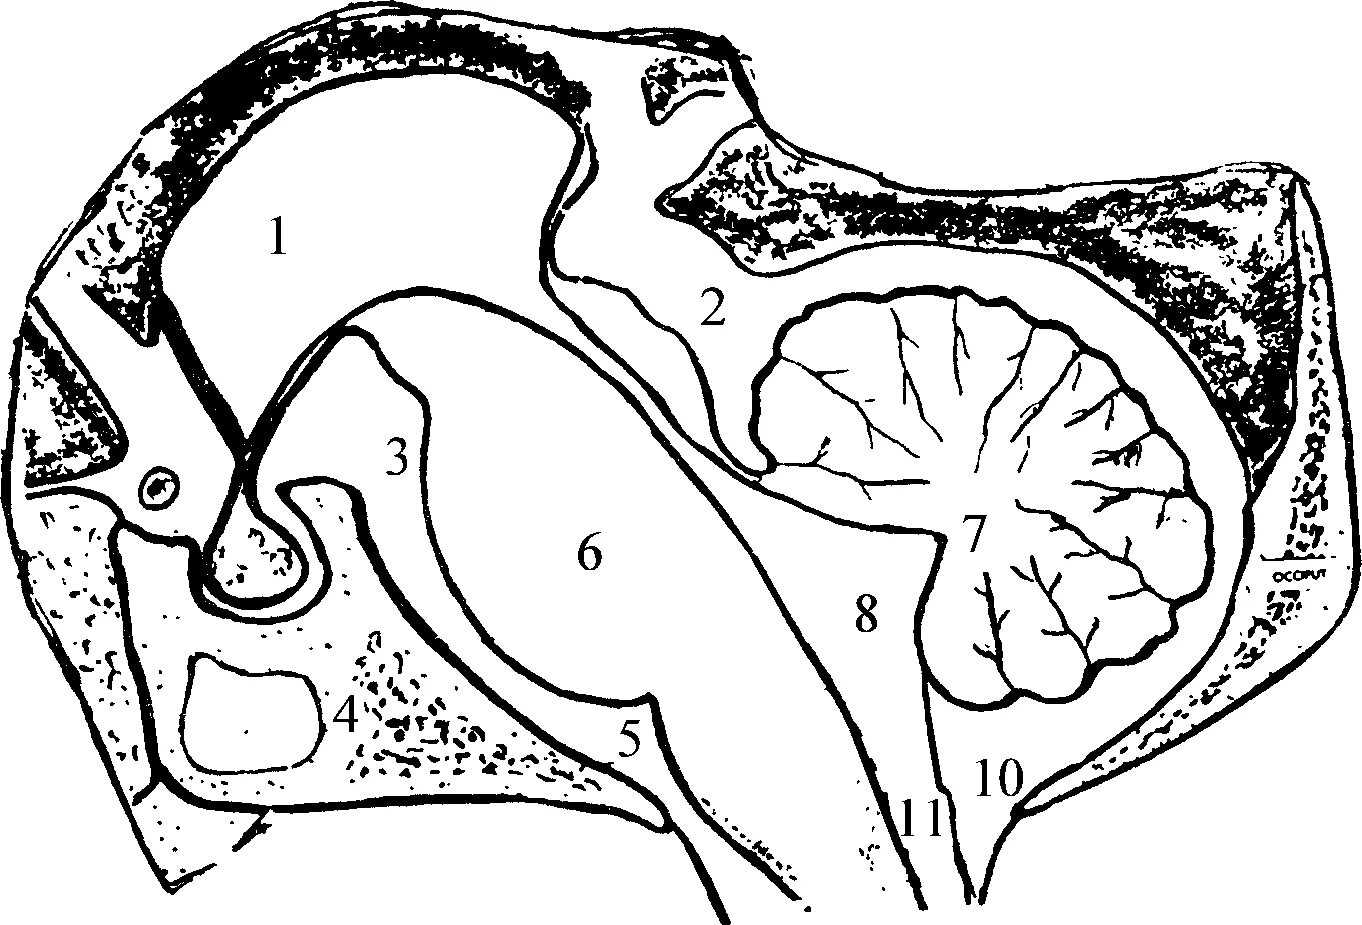

Цистерны на кт